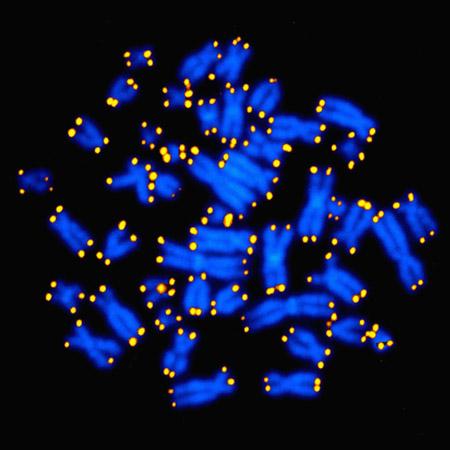

All six studies looking specifically at LTL found reduced telomere length in persons with PTSD. Leukocytes are white blood cells. Telomeres are stretches of protective, repetitive nucleotide sequences at the ends of chromosomes. These sequences shorten with every cell replication and are considered a strong measure of the aging process in cells.